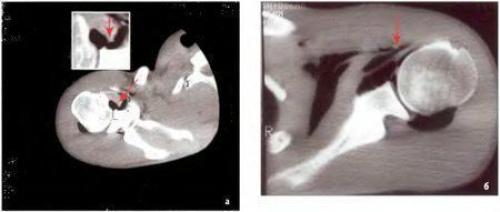

На КТ в аксиальной проекции признаки повреждения Банкарта — отрыв суставной губы от переднего края суставного отростка лопатки (1)

На КТ в аксиальной проекции признаки костного повреждения Банкарта — отрыв суставной губы от переднего края суставного отростка лопатки с костным фрагментом

На КТ в аксиальной проекции признаки дегенеративного истончения суставной губы и растяжения капсулы плечевого сустава

Повреждение Хилла-Сакса в виде импрессионного перелома задненаружного отдела головки плечевой кости

Таким образом, при компьютерной артропневмотомографии у всех пациентов с острой передней посттравматической нестабильностью плечевого сустава выявляют рентгенологические признаки классического повреждения Банкарта — отрыв суставной губы с капсулой плечевого сустава от передненижнего края суставного отростка лопатки и повреждения Хилла-Сакса — хондральный или компрессионный перелом головки плечевой кости.